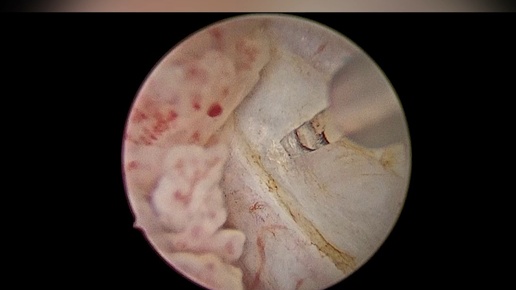

Лазерная en bloc резекция стенки мочевого пузыря с опухолью

Денис Давыдов врач-уролог, онкоуролог